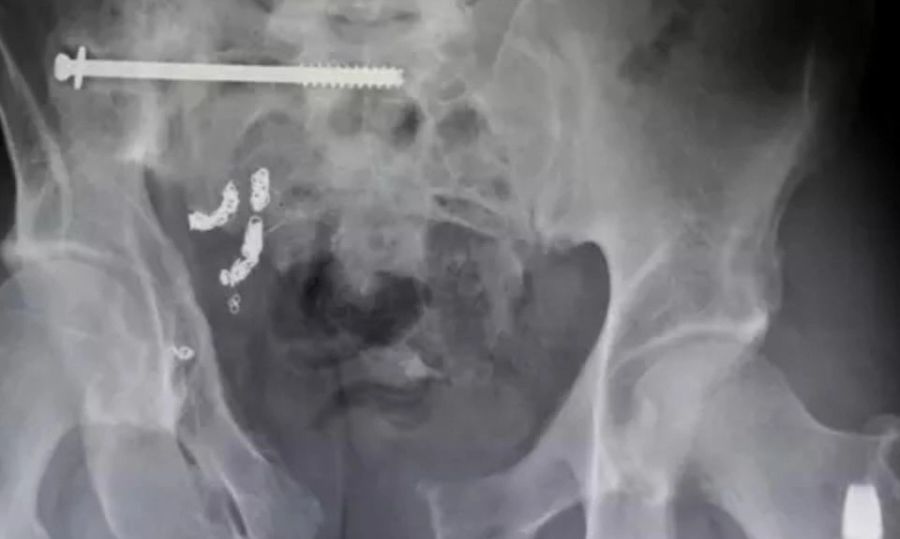

Χιλιάδες άνθρωποι νοσηλεύτηκαν το 2025 για ξένα αντικείμενα στα οπίσθια, με τις αμερικανικές αρχές να δίνουν στη δημοσιότητα μια λίστα… Περισσότερα...